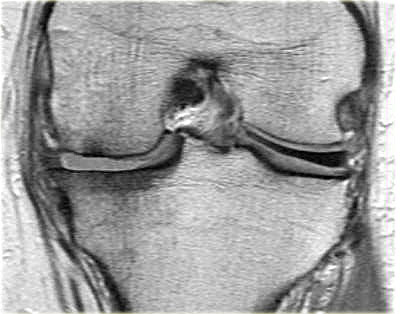

Như bạn đã đoán được qua tiêu đề của đoạn này, đây là một trường hợp sụn chêm lật (flipped meniscus).

Sụn chêm lật là một dạng đặc biệt của rách dạng quai xô (bucket-handle tear).

Sụn chêm lật xảy ra khi mảnh vỡ của sừng sau bị lật ra phía trước, khiến sừng trước của sụn chêm có vẻ to hơn bình thường.

- Thân sụn chêm ngoài.

- Sừng sau quá nhỏ và sừng trước có vẻ to hơn với đường viền không đều.

- Thoạt nhìn có vẻ như có một đường rách dọc ở sừng trước, nhưng thực chất phần sau của cấu trúc này chính là phần lật của sừng sau bị rách.

Cấu trúc phía trước là sừng trước.

Cũng cần lưu ý tình trạng phù tủy xương khu trú và dấu ấn lõm sụn khớp. - Cấu trúc phía trước là sừng trước.

- Một số bất thường ở phần sau.

- Phần sau di chuyển về phía đuôi (caudal).

- Trong hố gian lồi cầu là điểm nối giữa mảnh di lệch và phần còn lại của sừng sau.